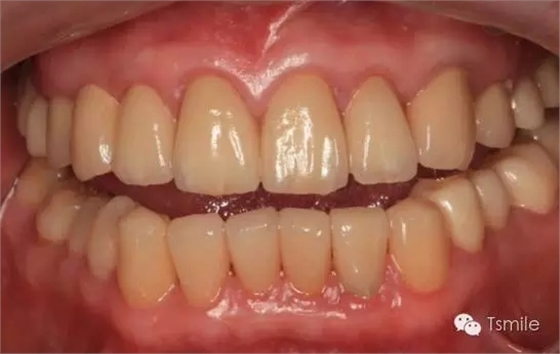

圖6:最終修復(fù)體完成 來源于tsmlie